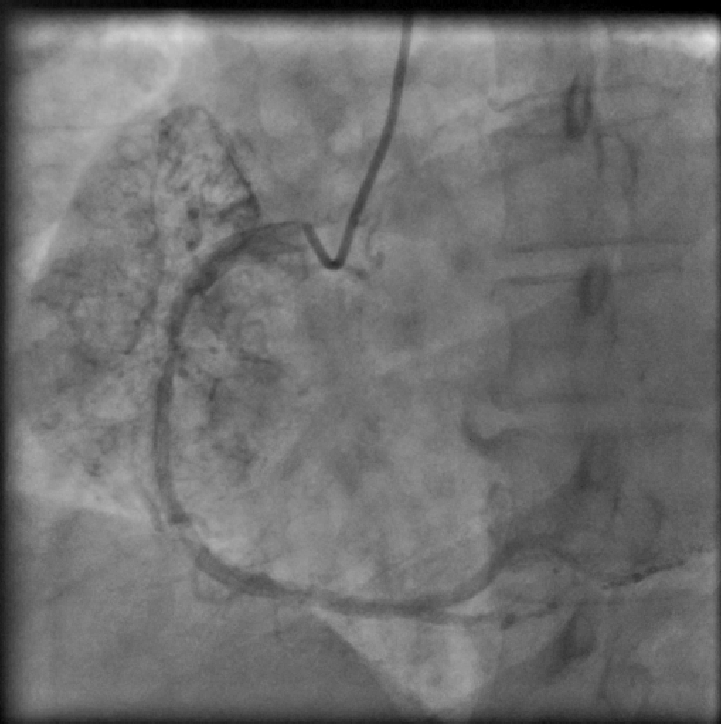

A 39-year-old female patient presented with complaints of retrosternal chest pain and shortness of breath associated with giddiness for the five days preceding the visit. She also complained of weight loss over the past two months. Six months prior, she underwent a coronary angiogram for similar complaints, which revealed normal epicardial coronary arteries with no atherosclerosis and an arteriovenous (AV) fistula in the right coronary artery (RCA). The patient had a history of hypertension and of pulmonary tuberculosis, which was treated medically.